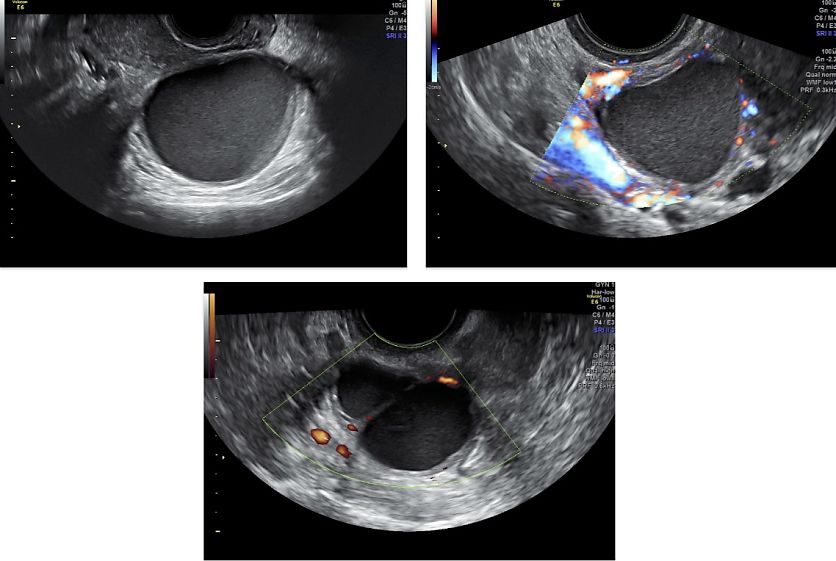

ENDOMETRIOMA

Endometriotic lesions in the ovary are often cystic, larger than lesions in other locations and contain blood with a dark brown color, explaining why endometriomas are often referred to as ‘chocolate cysts’. Due to shedding of intracystic endometrial foci, cyst fluid is produced, with at first no real cyst wall and only a thin layer of endometriotic tissue. Over time, however, processes such as fibrosis, acute and chronic inflammation, edema and necrosis lead to thickening and irregularity of the cyst wall.41 In pregnancy, decidualization of ectopic endometrial tissue may occur, which can result in increased solid components and enhanced vascularization within the cyst.

On ultrasound examination, typical endometriomas present as a cystic lesion with ground-glass echogenicity, with one to four locules and no solid components in a premenopausal patient (Figure 26). Of 713 histologically confirmed endometriomas in the International Ovarian Tumor Analysis (IOTA) studies, 65% were unilocular and 73% exhibited ground-glass echogenicity and 13% had low-level echogenicity.42 Atypical endometriomas are defined as unilocular-solid lesions with ground-glass echogenicity and a papillary projection, a color score of 1 or 2 and no vascularization inside the papillary projection (Figure 27).5 As per the recommendation of the IDEA consensus, the presence or absence of endometriomas should be described, as well as their number, size in three orthogonal planes and their ultrasound appearance according to International Ovarian Tumor Analysis (IOTA) terminology.43 Assessing vascularization by power Doppler may help in the differentiation between an endometrioma, a corpus luteum and a malignant lesion.44 A corpus luteum is characterized by strong circumferential blood flow (‘ring of fire’) and will generally resolve spontaneously after the menstrual cycle, unlike an endometrioma.

Ovarian endometriomas are associated with more extensive endometriosis, characterized by greater disease severity and the presence of multifocal DE.45 Whether or not endometriomas are present, the ovaries may appear adherent to each other and become fixed behind the uterus in the POD, a phenomenon known as ‘kissing ovaries’ sign (Figure 28). This finding points toward more severe pelvic adhesions, as well as a higher chance of bowel involvement and Fallopian tube obstruction.46

28

‘Kissing ovaries’ appearance with the left ovary attached to the uterine wall, suggestive of pelvic adhesions.